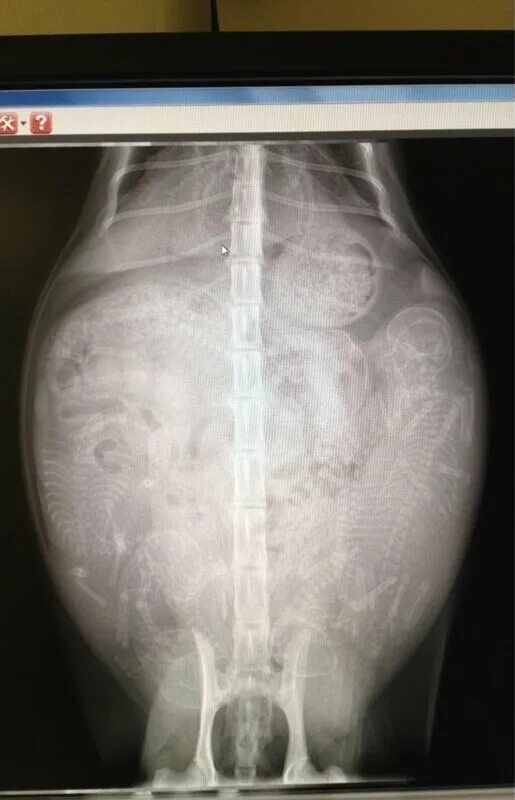

Делала рентген при беременности